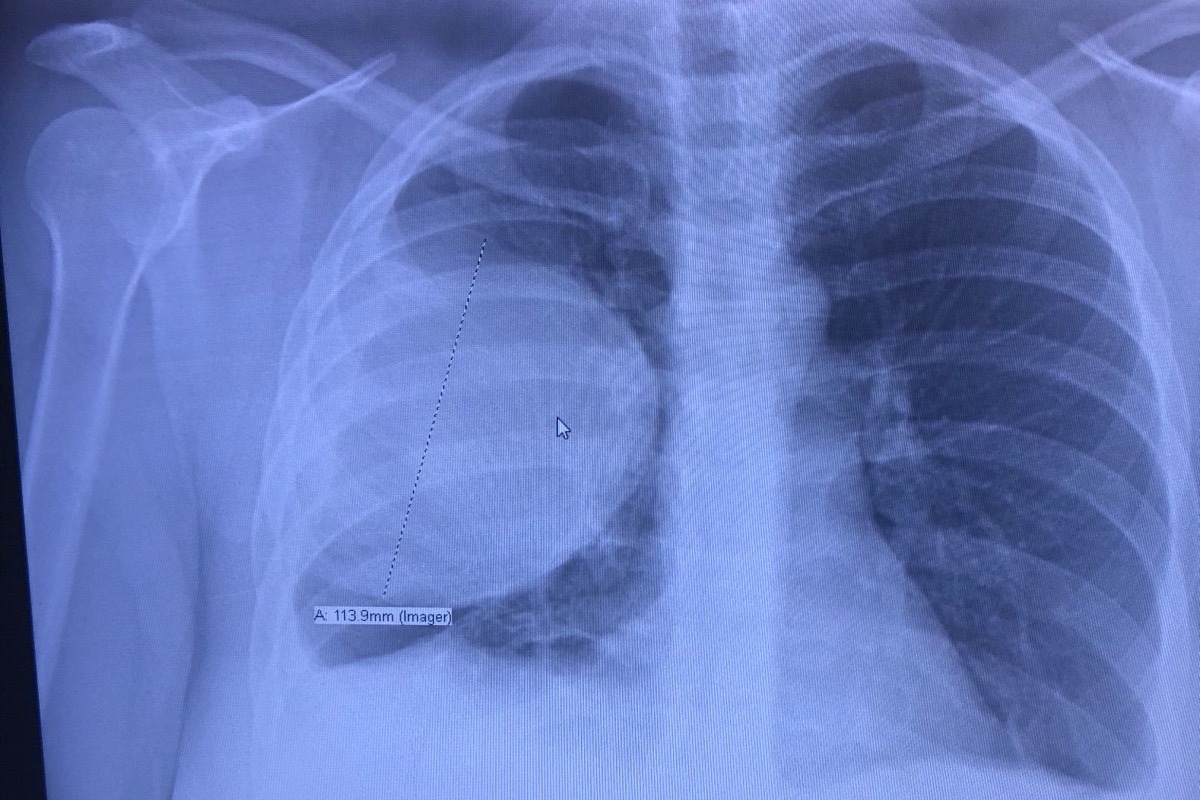

Friday, February 21st I was taking my CNA skills exam when I had a nasty coughing fit. It lasted about 5 minutes and very shortly after I had this sharp pain in my ribs and up to my breast and under my collar bone. I called my dad (cause I do anytime there’s an inconvenience in my life) and he said it sounded like I cracked a rib. I thought that made sense and I made a doctors appointment for Monday. By the time I got home 2 hours after, the pain was pretty unbearable. I didn’t leave my couch all weekend except twice a day to go to the bathroom and even then I’d cry just from walking and sitting on the toilet. Monday comes around and I make my way to the doctors and get some X-rays done. They found a large mass on my lung, my oxygen was at 88 and my pulse was at 156. The doctor came in and let me know what was going on, and that they’d be transporting me to Hendrick medical center by ambulance. They got me to the emergency room where they also told me I had pretty severe pneumonia and a small nodule under the mass that they thought was Tuberculosis. I was in isolation, and on sepsis precaution. After about 6 hours in the ER, a CT scan and lots of drugs- I finally went up to a room where I stayed for 8 days. I had an additional CT scan as well as a complete bone scan. The first two doctors I saw along with the radiologists said they were not comfortable going in for biopsy because they could not identify what the mass was. After 2-3 days, they called the cardiovascular surgeon to see if he could crack the case. He decided he would go in through my wind pipe and take a sample of enflamed nodules that had actually been there since 2012 and not gotten any bigger. He also went in through 5 entry points on my side for the robotic arm something or other (I will find the name of the actual procedure). He took a couple of samples from different places on my lung and bronchioles(I think is the word) and sent them right away for samples and all of the samples came back NEGATIVE for cancer and I was out of surgery in 3-4 hours. I also had a chest tube inserted because the doctor thought this was a hematoma. Quite a bit of blood did drain out though. I will include pics of the drain. After 4-5 more days in the hospital, I was released and under the impression that everything was gonna be just fine. I came home and have been resting. Still pretty sore and uncomfortable, but okay. Monday (March 9) I had my post-op appointment. They called me the day of and told me my appointment was being changed to an hour later so I could see the doctor instead of his PA. No big deal, I figured he just wanted to personally see how I was doing. Unfortunately at my appointment he told me that the samples were sent to Dallas for further testing and the mass came back as cancerous. They said it looks biologically identical to the cancer I had when I was 12. I have not seen an oncologist yet so we don’t have much of a game plan but after I’m fully healed from surgery I will be getting a PET CT scan of my entire body, as well as an MRI of my brain to check to see if it has metastasized anywhere else. At this point, I’m not able to get the PET CT scheduled until I get a payment plan set up since it’s such an expensive scan. My hospital bill currently is $164,000 and my ambulance bill is $800. I’m out of work and will be until my doctor clears me to work again and since CNA work is very physical, it likely won’t be very soon. Especially depending on what route they take for treatment. I know this was long, so thank you for reading and for any donations. Thoughts and prayers are VERY appreciated. Please feel free to share.